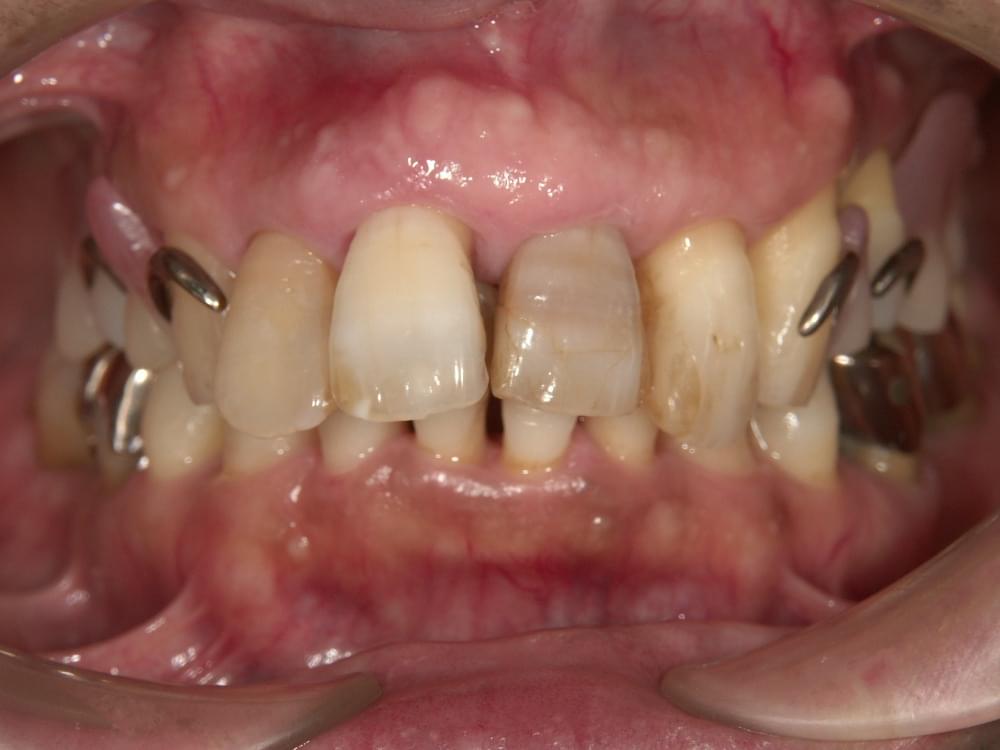

歯周病治療プログラムの治療例4

- 歯の根元が割れていると言われ抜歯が必要と言われた

- 全てのセラミックを入れている箇所で歯周病になっていると2,3年かよっているがよくならない。

せっかくセラミックを入れれば良くなるかと思ったのにショック

私(長島)からの提案として

なぜ歯周病になってしまうのかを根本的に調べたほうがいいですよと伝えた。

歯周病になってしまうのは、患者さんはブラッシング方法がダメだからっと思っている方が多いが、中にはブラッシングをあまりしなくても歯周病にならない方がいますし、逆に1日3回ブラッシングしても歯周病が改善しない方がいますので、○○さんの歯周病になった原因を特定したほうがいい。

まずは精密検査をされて、○○さんの歯周病を見つけることが最優先課題とお伝えしました。

治療の概要

治療内容

行動科学に基づき、「自分の歯は自分で守る」という意識改革や行動変容を促しながら、スケーリングや歯ブラシ・フロス指導を行いました。

治療期間・回数・時間

1.5ヶ月・5回・計5時間

費用

29,500円+税

リスク・副作用

歯肉の痛み・出血